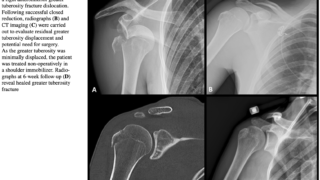

午前の病院での仕事今朝は降雪があり, うっすらとクルマに雪が積もっていました.道路はノロノロ運転のクルマが多く, いつもよりも通勤に時間を要しました.8時前に病棟に上がって, 電子カルテを確認.昨晩は, 当院が整形外科の救急輪番日.上腕骨骨...